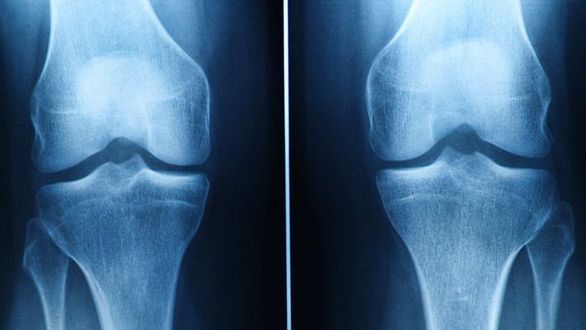

Mężczyźni cierpiący na osteoporozę są dwukrotnie bardziej narażeni na zgon z powodu powikłań tej choroby niż kobiety - powiedział dziennikarzowi PAP dr Waldemar Misiorowski podczas międzynarodowego kongresu poświęconego tej chorobie, który odbywał się w Rzymie.

Osteoporoza kojarzona jest przede wszystkim z kobietami i to głównie z tymi, które są po menopauzie. Tymczasem prawdą jest jedynie to, że kobiety częściej chorują z powodu tej choroby.

- Gdy jednak osteoporoza już rozwinie się u mężczyzn, to są oni bardziej narażeni na zgon z powodu powikłań po złamaniach kości, do jakich często doprowadza to schorzenie - powiedział dr Misiorowski, endokrynolog z Centrum Medycznego Kształcenia Podyplomowego w Warszawie.

Specjalista podkreśla, że mężczyźni nie są w ogóle świadomi tego zagrożenia. Polacy w ogóle mało wiedzą o osteoporozie, nawet kobiety. W przypadku mężczyzn jest jeszcze gorzej, bo przeważa wśród nich przekonanie, że oni nie chorują na osteoporozę. A to błąd. Przewaga męskiej populacji polega jedynie na tym, że mężczyźni z reguły mają większą masę kostną. Dzięki temu zwykle o 7 lat później dochodzi u nich do złamań związanych z osteoporozą, która objawia się niską masą kostną i upośledzoną mikroarchitekturą tkanki kostnej. U mężczyzn złamania kości występują dwa razy rzadziej niż u kobiet. Gdy jednak choroba ta rozwinie się, ryzyko zgonu jest u nich dwa razy większe.